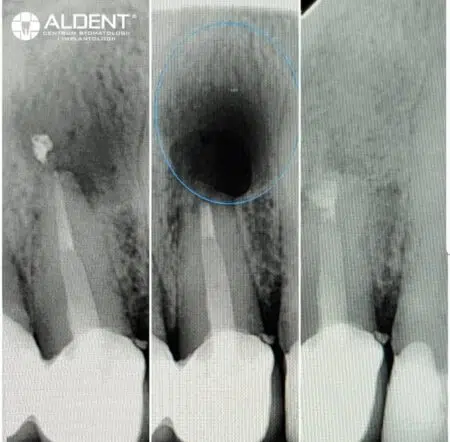

Pierwszym krokiem w leczeniu zatrzymanych zębów jest szczegółowa konsultacja stomatologiczna i diagnostyka. Wykonujemy panoramiczne zdjęcia rentgenowskie oraz stożkową tomografię komputerową, aby dokładnie ocenić położenie zatrzymanego zęba oraz jego wpływ na otaczające tkanki i struktury zębowe.

Resekcje wierzchołków korzeni zębów to skuteczna metoda leczenia stanów zapalnych w tkankach okołowierzchołkowych, które mogą wystąpić po nieprawidłowo przeprowadzonym leczeniu kanałowym. Ten zaawansowany zabieg chirurgiczny pomaga uratować ząb przed koniecznością ekstrakcji, eliminując źródło infekcji i przywracając zdrowie jamy ustnej.

- Diagnostyka i Planowanie

- Przed przystąpieniem do zabiegu wykonujemy szczegółowe badania diagnostyczne, w tym zdjęcia rentgenowskie i tomografię komputerową, aby dokładnie ocenić stan korzenia zęba i otaczających tkanek.